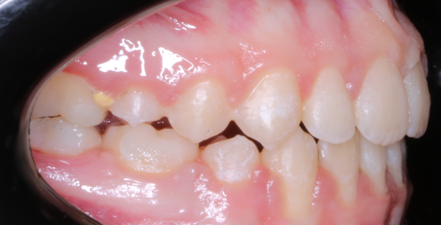

Llama la atención a primera vista la mordida abierta bilateral, especialmente pronunciada entre el cuadrante 1 y 4 debido a una interposición lingual en posición estática. Entre otros hallazgos fundamentales, observamos: un patrón dolicofacial severo (VERT: -2), una compresión de la arcada superior que cursa con un perfil y relación oclusal de clase III y la rotación del 35 y 45. Este caso se trató con un disyuntor, exodoncias de 44 y 34, brackets convencionales y educadores para rehabilitación de la lengua en un tiempo de 22 meses. Aunque estoy satisfecho con el resultado final, me hubiera gustado clavar la interscuspidación de premolares en el cuadrante I y IV, y mejorar la relación oclusal de cuadrante II y III. Sin embargo, lo bonito, es que hay a veces, en la ortodoncia real, que el paciente está satisfecho y quiere terminar antes de tiempo, o por el contrario, que el profesional intenta pero no consigue el resultado deseado. Y a mí más que compartir casos perfectos, me gusta mostrar mis errores, mi realidad.

La ilustración nos deja entrever algo tan fácil como que en un paladar pequeño no entra una lengua grande. Y viceversa, en un paladar grande entra una lengua grande. Llevándonos dicha explicación al caso que nos atañe, podemos ver  en la fotografía lateral del lado derecho como la lengua escapa y busca espacio, de manera permanente, entre el cuadrante 1 y 4,  estímulo que mantenido en el tiempo generó en una mordida abierta lateral.